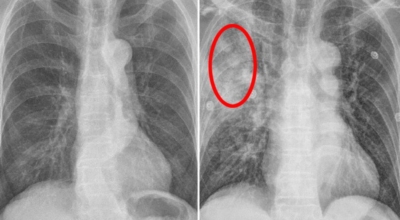

1. 금연

긴 시간의 흡연은 기도의 보호 메커니즘을 훼손시켜 기관, 기관지, 폐 간질 또는 폐에 훼손을 주어 폐 기능의 건강에 영향을 미칩니다.